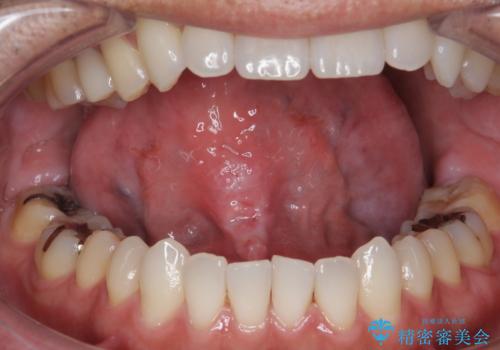

[ 舌小帯の形成 ] 滑舌の改善をしたい

担当医 大元洋佑

![[ 舌小帯の形成 ] 滑舌の改善をしたいの症例 治療前](https://seimitsushinbi.jp/wp/wp-content/uploads/2022/09/459b5062738498b637cd13998f29068e-500x350.jpg?v=1662343519)

![[ 舌小帯の形成 ] 滑舌の改善をしたいの症例 治療後](https://seimitsushinbi.jp/wp/wp-content/uploads/2022/09/2f7669bb326f4f515756a383a61feb88-500x350.jpg?v=1662343538)